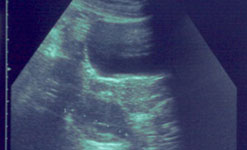

|  |  | An ultrasound scan showing PCOS cysts on an ovary |

Polycystic Ovary Syndrome

In this week’s Check Up, Barbara Myers and her guest Professor Adam Balen from Leeds General Infirmary will be offering advice about Polycystic Ovary Syndrome.

Weight gain, excessive body hair, acne and irregular periods are just some of a myriad of symptoms that women with polycystic ovary syndrome (PCOS) can suffer from.

The syndrome is triggered by an imbalance in some, or all, of the hormones that control the menstrual cycle. Many women with the condition have raised levels of the hormone insulin. This causes the ovaries to produce an imbalance in hormones, including an overproduction of testosterone.